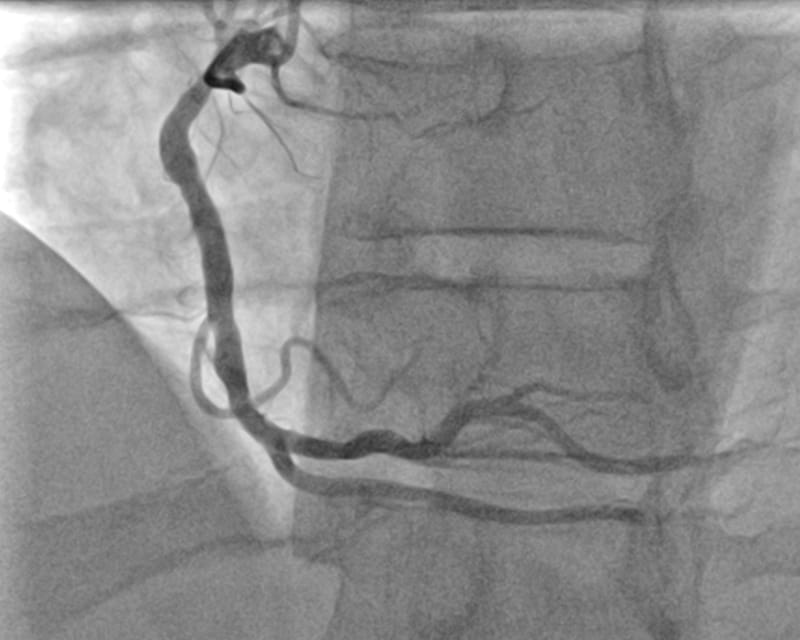

Angiography, angioplasty and stenting